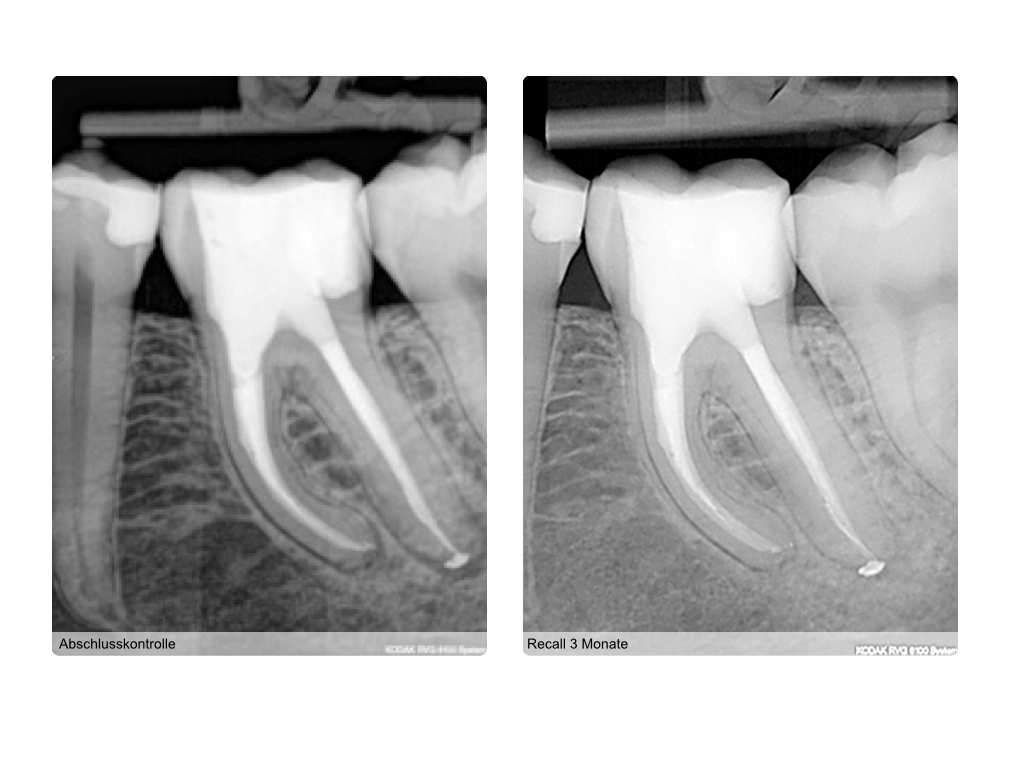

WS4.005

Instrumentenfrakturen (1)